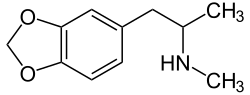

Entaktogene und Empathogene

Als Entaktogene (Adjektiv entaktogen, „das Innere berührend“, aus griechisch en, „innen“, lateinisch tactus „berührt“) und Empathogene (empátho; altgriechisch ἐμπάθω, „mitfühlen“; vergleiche Empathie; -gen von altgriechisch γένεσις, génesis, „Entstehung“) werden psychoaktive Substanzen bezeichnet, unter deren Einfluss die eigenen Emotionen intensiver wahrgenommen werden. Der Terminus Entaktogen wurde von dem US-amerikanischen Chemiker David E. Nichols in den 1980er Jahren eingeführt.[98] Zu jener Zeit wurden diese Substanzen auch in der umstrittenen Psychotherapie mit Psychedelika eingesetzt, da sich der Patient seiner eigenen Psyche besser bewusst wird und somit der Zugang zu seinem Unterbewussten erleichtert wird. Beide Termini werden synonym verwendet. Viele Entaktogene, wie z. B. 3,4-Methylendioxyamphetamin (MDA), 3,4-Methylendioxy-N-methylamphetamin (Ecstasy, MDMA), 3,4-Methylendioxy-N-methylcathinon (bk-MDMA, MDMC) wirken als Releaser (Ausschütter) der endogenen Monoamin-Neurotransmitter Serotonin und Noradrenalin, was zu einem unüblich erhöhten Spiegel dieser Botenstoffe im Gehirn führt.[99]